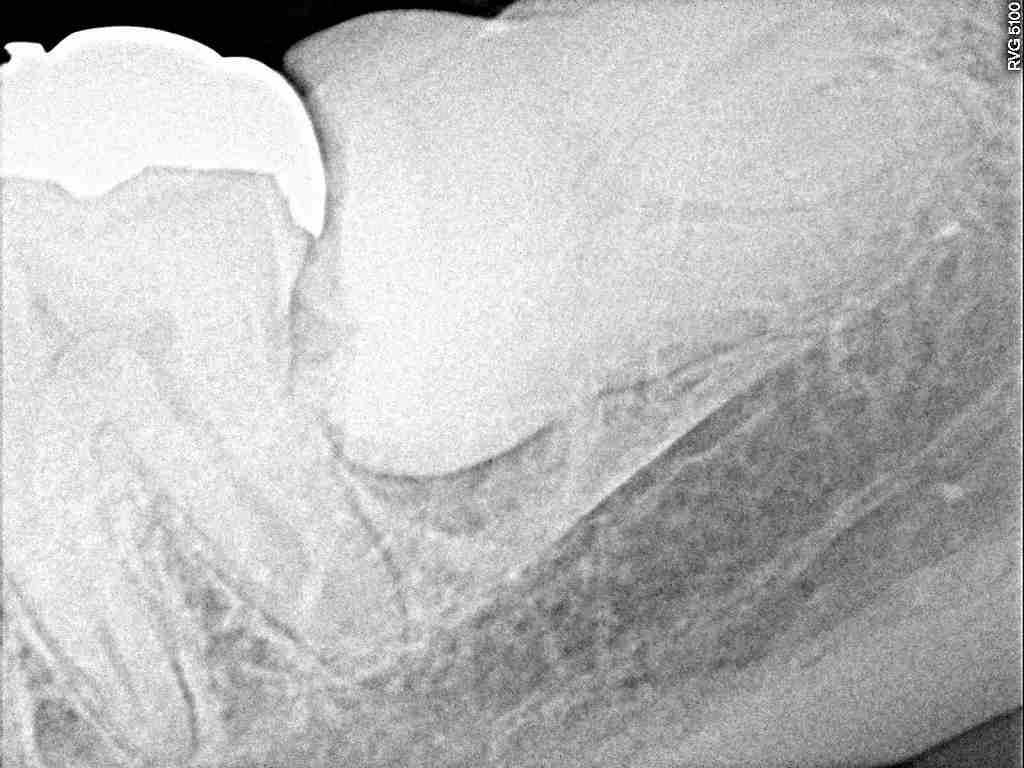

横に向かって生えています

かなりの大きさの親知らずが横たわっています

歯冠部の下に化膿して骨吸収が認められます

この方は将来歯周病の要因で歯を失われる体質かどうかも

ここを見ればわかります

2根性で抜きにくくなっていました

根が2根で湾曲していました